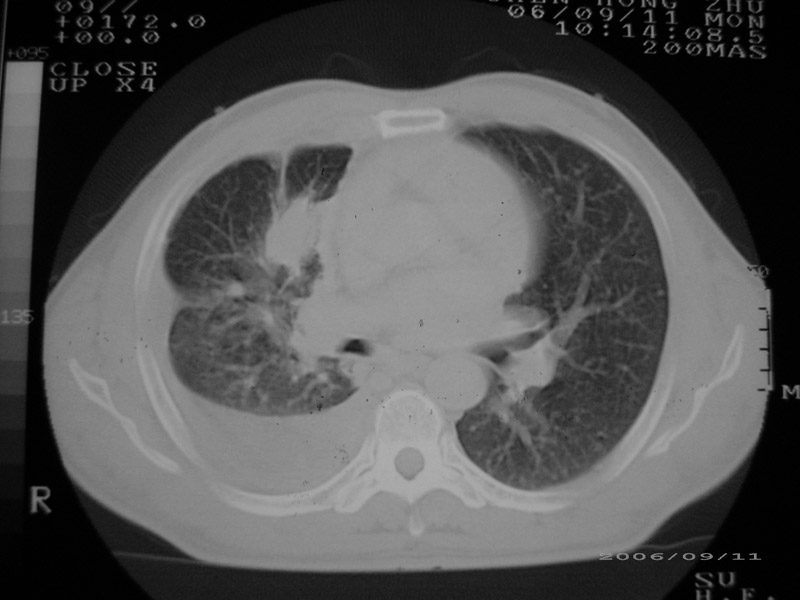

以下是引用守望可可西里在2006-9-11 15:29:00的发言:[br][br] ct平扫表现:右侧胸膜腔缩小,积液,胸膜增厚且不均匀、不规则,以纵隔胸膜增厚为主,边缘呈锯齿状,并见附壁内突之结节状肿块影。右肺含气量减少,纹理聚集,右肺门中下部见数个肿大的淋巴结。纵隔无移位,内未见明显肿大淋巴结,双侧主支气管以及各叶、段支气管比较通畅。。[br] 考虑:右侧胸膜恶性间皮瘤,伴肺门淋巴结转移。